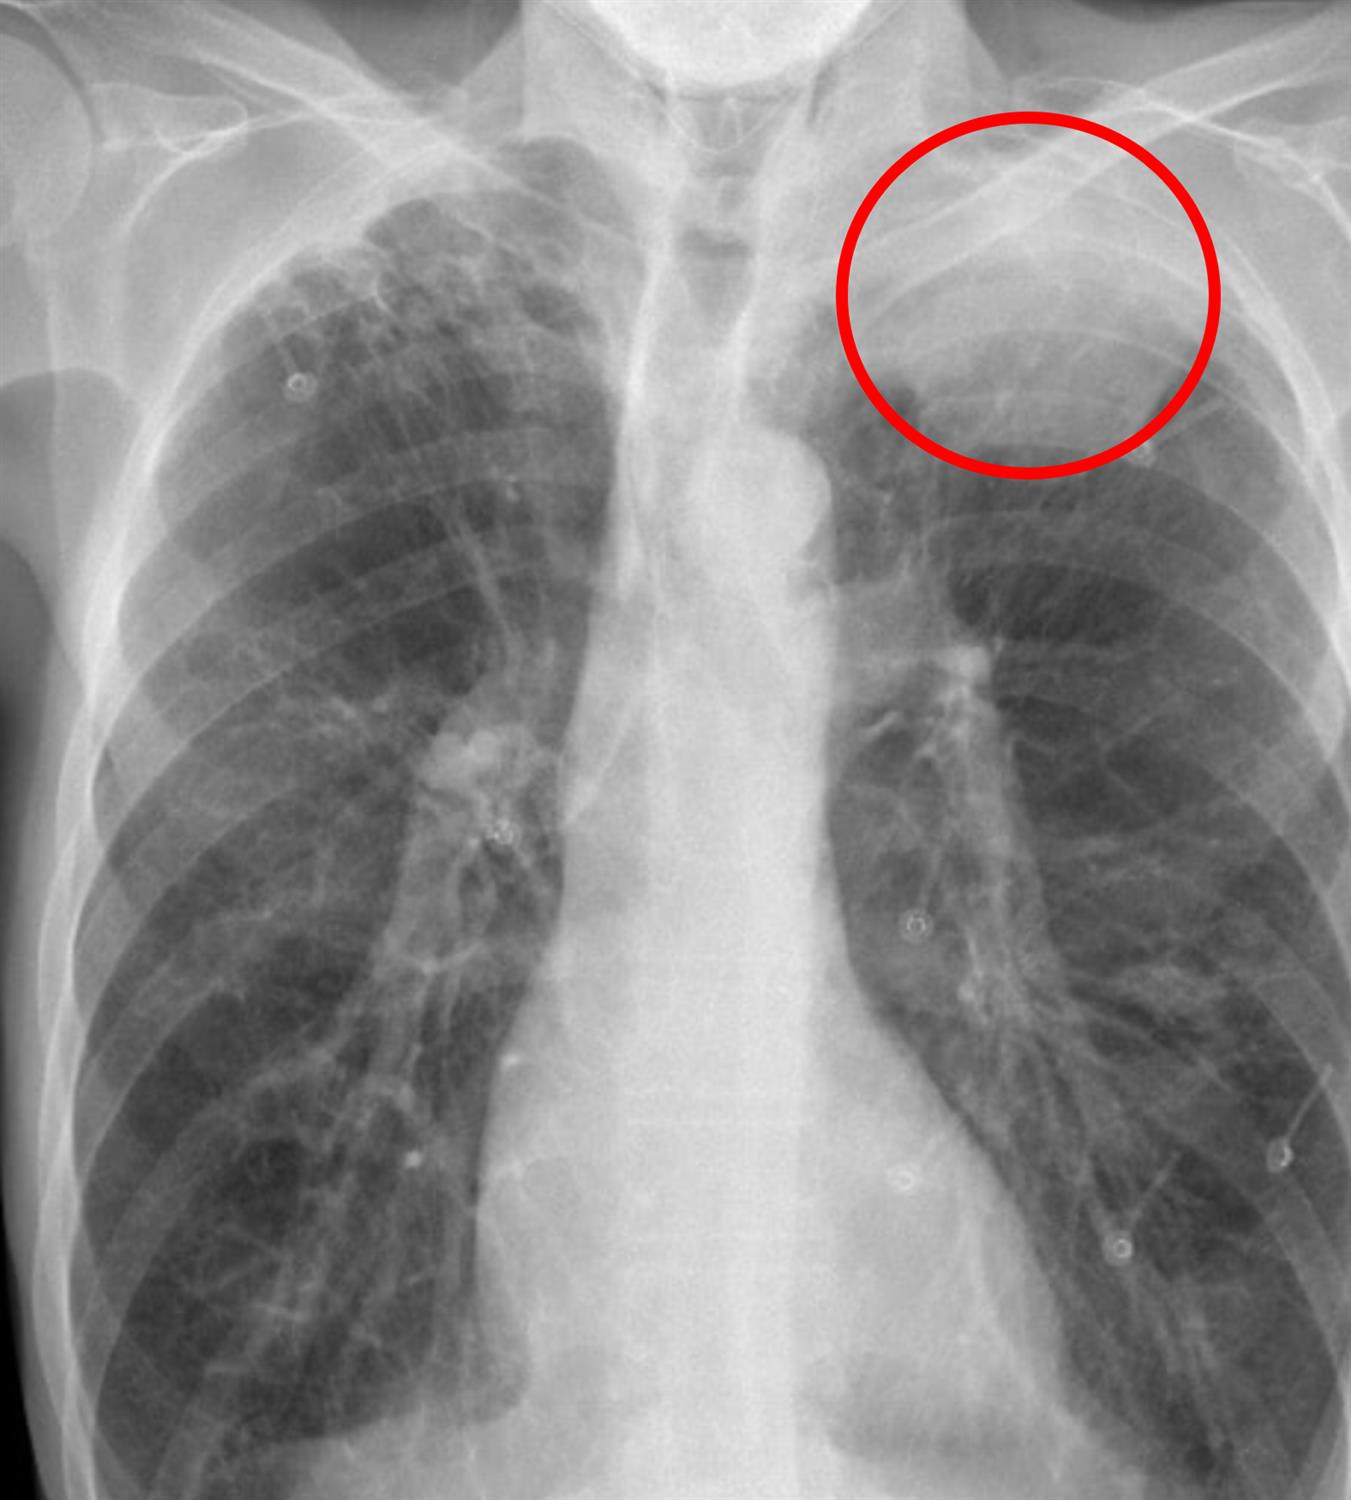

A 73-year-old man presents to his primary care physician with a 2 month history of shortness of breath. He started noticing the symptoms while playing tennis with his friends, but his symptoms have gotten worse over time. He has worsening pain in his right shoulder and episodes of hemoptysis as well. He has a history of coronary artery disease and underwent an uncomplicated coronary angioplasty with stent placement 2 years ago. He worked as a shipyard engineer for his career and has a 30-pack-year smoking history. He drinks 2-3 drinks per week. His temperature is 98.7°F (37°C), blood pressure is 141/79 mmHg, pulse is 97/min, and respirations are 13/min. Physical exam is notable for right pupillary constriction as well as paresthesias in his right fourth and fifth digits. There is no pain with active shoulder rotation. His chest imaging is shown in Figure A. Which of the following is most likely responsible for the patient’s symptoms?

Figure/Illustration A is a chest radiograph that demonstrates an apical lung mass (red circle). This finding is classically seen in patients with a Pancoast tumor.

Pancoast tumor presents with shoulder pain, cervical radiculopathy, Horner syndrome, and hoarseness and should be suspected in a patient with a smoking history and an apical lung mass on imaging.